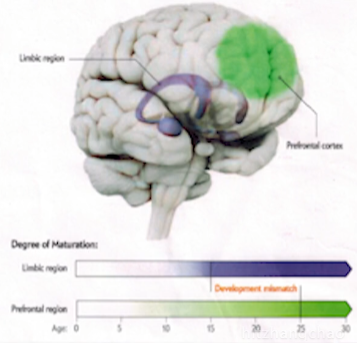

- 情绪比理智重要,人受情绪控制比理智大

- 绿色是我们的理智,紫色是我们的情绪

图4-1 - 情绪成熟早,理智成熟晚

- 情绪是大路,理智是小路

- 人不是理性的动物